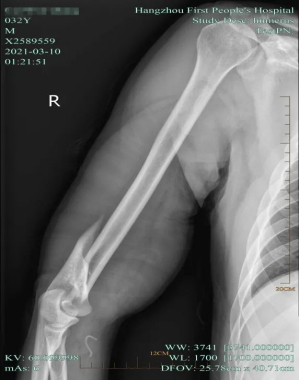

一年多前,他接诊过一例扳手腕骨折的病例至今印象很深。也是一个小伙子,酒后和朋友扳手腕后,手臂一阵剧痛,马上肿起来了。到医院一检查,发现发生了“肱骨干断裂”,而且情况很严重,骨头已经变成了“螺旋状”。

最后,因为他的螺旋形骨折移位太严重,没办法保守治疗,最后采用了手术用钢板内固定。“可以说是因为一个小游戏,吃了大苦!”江医生说。